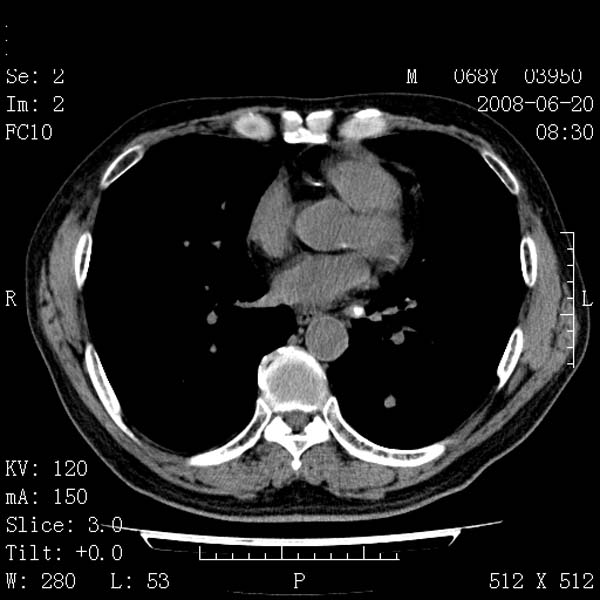

以下是引用守望可可西里在2008-6-24 1:11:00的发言:[br][br] 考虑为周围型肺癌:[br] 1.分叶结节,形态极不规则,蟹足样伸展的恶性浸润特征比较明确。[br] 2.磨玻璃影中由多个更高密度小结节聚集呈梅花瓣样。[br] 3.局部胸膜凹陷征比较明确。[br][br] 另:纵隔胸膜明显增厚、粘连。

以下是引用zjzjr在2008-6-24 11:19:00的发言:[br]支持左下肺周围型肺癌伴右肺转移,纵隔淋巴结转移,心包积液.

以下是引用zhangling在2008-6-24 14:56:00的发言:[br]我们科室意见报告为[br][br]1考虑左下肺周围型肺癌[br]2右肺小结节考虑转移瘤,纵隔淋巴结转移[br]3心包积液. [br] 各位老师分析的相当好 谢意[br]